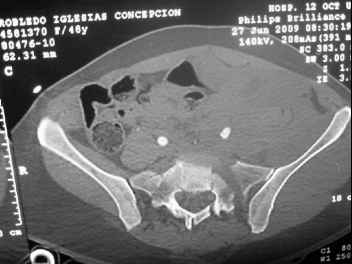

I'm posting this case on behalf of Dr. Pedro Caba, he is unable to post but able to read. 41 yo female , fall from 10 meters five days ago. Hemodynamically unstable on admission treated by angio and embolization and skeletal traction, with no external support. No associated injuries. Based on CT scan the pt has a both column fracture with conminuted dome and displaced anterior column and a sacral Denis 1 fracture with a displaced left ala. I think the best approach for the acetabular fracture is ilioinguinal with Smith-Petersen extension but don't know exactly the sequence . Will you start with the sacral fracture? Which technique? Thanks in advance Pedro Caba Unidad de Trauma Hospital 12 de Octubre Madrid Spain

The soft tissues are also in mild condition, buttock hematoma and probably a Morel-Lavalle. I send some more CT images. There are some conminution in the posterior column (I don’t have images now). The patient is scheduled for surgery next Monday. The plan is percutaneous sacral fixation and then ilioinguinal approach .

This complex and displaced sacral injury is likely an H pattern...2 hemipelvic components, an upper sacral component which remains attached to the lumbar spine, and a caudal sacral component...there are typically anterior ring injuries as well...in this patient's example, the left sided acetabulum also has been exploded.

Most H pattern sacral fractures have the transverse fracture limb of the "H" at the upper-second sacral segment junction or disc region...some fracture thru the second segment, and some or at other sites...but most yield thru the upper-second sacral segments junction...with variable traumatic associated neurological findings.

The transverse fracture limb liberates the upper sacral segment and its attached lumbar-thoracic-cervical spine to displace...usually anteriorly and in kyphosis.

The kyphosis and anterior translation of the upper sacral segment distorts the safe area for iliosacral screw usage...the imaging allows the surgeon to preoperatively plan if iliosacral screw fixation is a safe possibility.